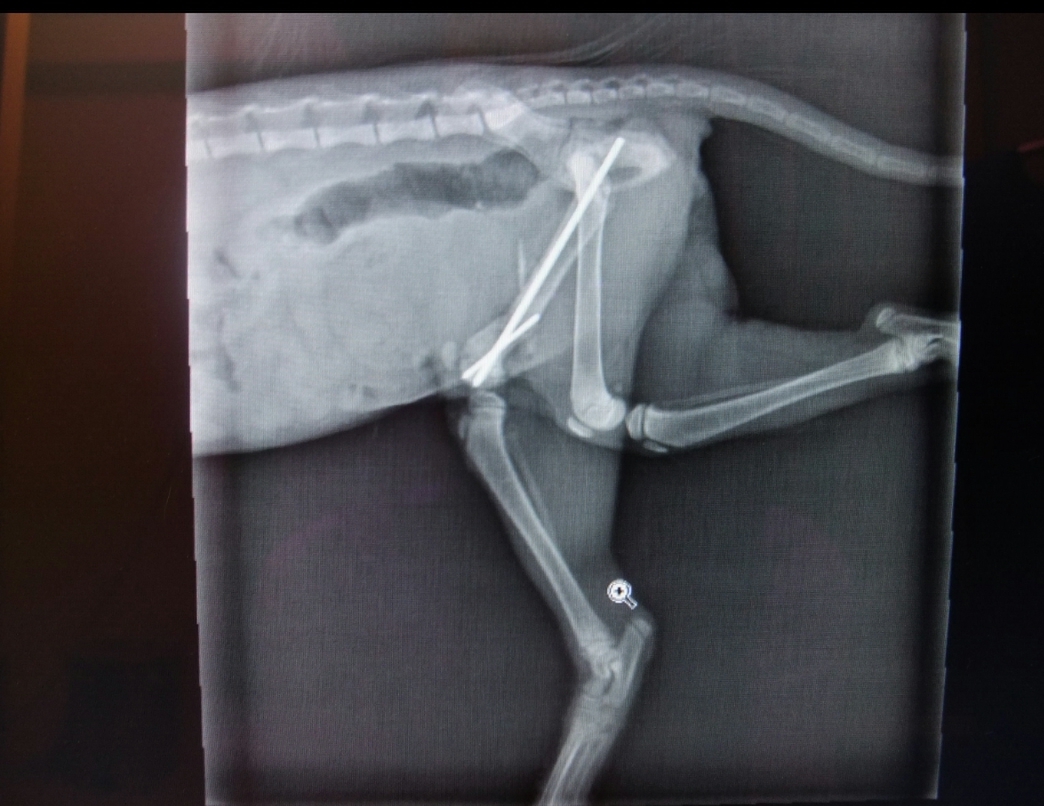

主題: 三個月小貓大腿粉碎性骨折癱軟在路中央險些被輾 申請者姓名: 康庭瑀 花色: 申請日期: 2013-11-27 18:07:58 申請者部落格: 申請者臉書網址: 所在縣市/合作醫院: 台南市/啄木鳥動物醫院 治療費用: 18950元 需求人數: 21人 已結案 (2014-01-10 17:50:13) 報名人員: Wendy x2(已付款)、Milkbau Lu(已付款)、vivian(已付款)、Jocelyne YuYu Kao(已付款)、臺北市支持流浪貓絕育計劃協會(代MD饅頭希望報名)(已付款)、蔡秀芳、小揚、王千枝 x2(已付款)、Cha-Mei Huang(已付款)、Bubu Wang(已付款)、林建華(已付款)、Wendy Tseng(已付款)、David Wei(已付款)、Crystal x4(已付款)、ERic YU(已付款)、林學凱(已付款)、chiawei x2(已付款)、 候補人員: 動物病情說明: 11/14下午約17:20左右,我要騎車去買東西,隱隱約約看到路中央有個白色東西,騎近一看,是隻小貓,車水馬龍,差點被車輾過!路上人車趕下班的趕下班,買東西的買東西,就是沒有人肯伸出援手拯救牠,就連把牠移到路邊也不肯。基於愛護流浪貓咪的精神,我馬上把他撈起來放在路邊,發現他不能走路,只能用爬的,且還有外傷,身體很臭,一身白毛染成灰黑色,且感覺很餓,不知道幾天沒吃東西了,又受傷又沒東西吃,貓是愛乾淨的動物,身體卻髒兮兮的,真的很可憐。於是我馬上送到附近的獸醫院,醫生說他大腿骨折了,但自家沒有儀器可檢查,需送至台南市區,於是我馬上帶小貓衝去市區先施打消炎針、照x光,發現一隻大腿粉碎性骨折,獸醫院說必須先住院觀察才能開刀,抽血檢查發現小貓肝指數很高,必須施以打針跟藥物治療,且白血球也很高,不排除傷口有感染的情況,還脫水,情況非常糟糕。於是當晚就住院了,由醫護人員悉心照料,第二、三次抽血檢查肝指數和白血球的情況有慢慢好轉了,但是脫水情況改善了,卻發現有貧血的問題,所以還另外驗了血型,開刀手術額外了輸血的步驟。開完刀後小貓就繼續住院,食慾體力恢復得很好,等拆完線就能出院了。 動物近況說明: 11/20開刀,用了骨釘,狀況良好,等拆線出院